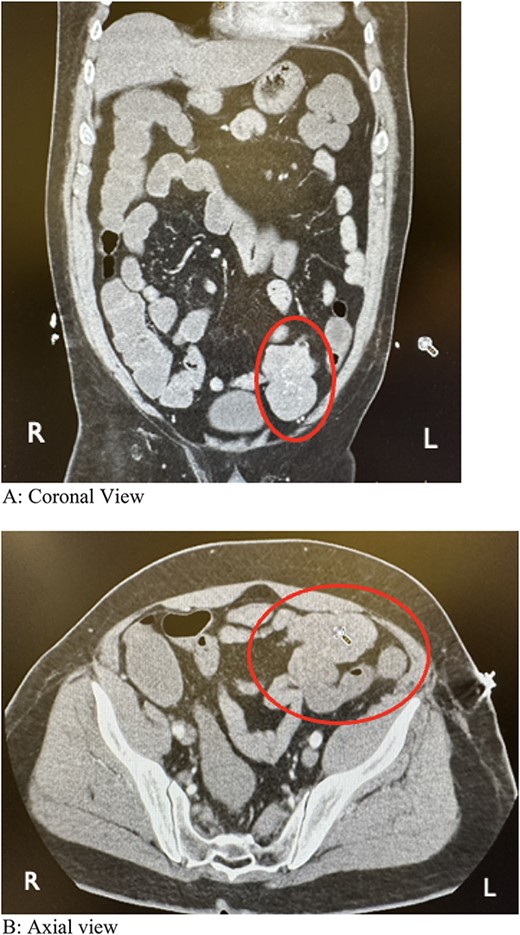

During colonoscopy, the mucosa of the entire colon appeared unremarkable. However, black tarry stool was detected, extending from the transverse colon to ~20–25 cm into the terminal ileum, which was successfully intubated. Despite a thorough examination, no bleeding source or additional abnormalities were identified. Subsequent computed tomography angiography (CTA) of the abdomen and pelvis revealed a lobulated soft tissue mass adjacent to the distal small bowel loop, measuring 5.7 × 3.5 × 7.4 cm, concerning for small bowel tumor versus mesenteric tumor in the left lower quadrant (LLQ) (Fig. 1A and B). Following discussion of the CT results, the patient, who had been initially reluctant to provide his medical history, described experiencing a slowly progressive sensation of dull ache and bulge in the LLQ since his teenage years, accompanied by intermittent episodes of abdominal cramping and pain, along with changes in stool patterns. Despite experiencing these symptoms over several decades, investigations were conducted intermittently without imaging, with the symptoms being attributed to functional causes without identifying an underlying cause.

Computed tomography angiography showing a lobulated soft tissue mass associated with distal small bowel loops in the left lower quadrant. (A) Coronal view. (B) Axial view.